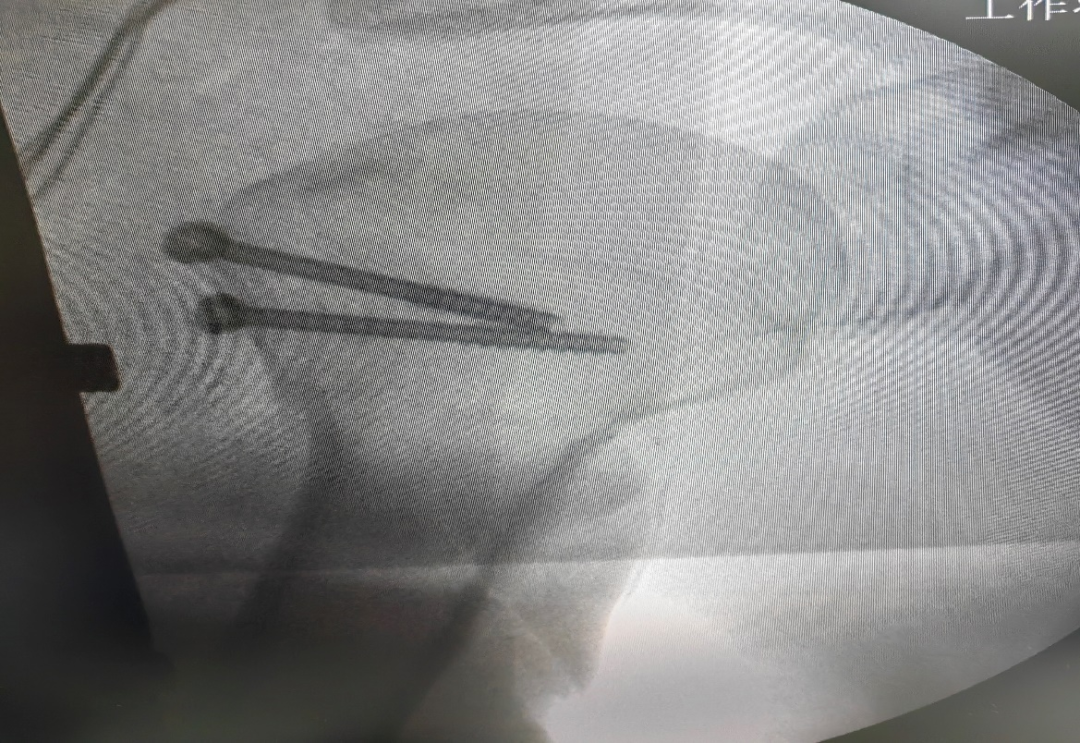

近日,我院骨科成功开展肩关节镜下大结节骨折内固定+肩袖修补术。患者,男,46岁,因右肩摔伤肿痛活动受限入院。CT示:右肱骨大结节骨折。MR检查提示:右冈上肌腱损伤。完善术前准备后,行“肩关节镜下右肱骨大结节骨折内固定术+肩袖修补术”,手术非常顺利,术后我院康复团队介入早期康复,加快了患肩功能锻炼的进程,患肩功能恢复良好。

肱骨大结节骨折是肱骨近端骨折中常见的骨折类型之一,肱骨大结节骨折后肩袖肌腱的力臂遭到破坏,特别是在肩关节外展时,严重影响了肩关节功能。移位的大结节减低了肩峰下间隙,导致肩关节在外展活动时出现撞击,使肩关节的功能和活动范围受到影响。因此,治疗移位明显的肱骨大结节骨折不但需要坚强固定,同时需要解剖复位。随着肩关节镜的发展,关节镜下治疗大结节骨折已被越来越广泛的应用。关节镜下可采用空心钉、克氏针、双排锚钉(双线桥)等方式进行固定,根据不同骨折类型可以多种术式相互结合使用。对肱骨大结节骨折块较小、粉碎严重的骨折难以达到解剖复位,坚强固定,术后容易出现内固定失效,因此对于肱骨大结节粉碎性骨折,建议采用双排锚钉缝线桥技术固定大结节骨折,内、外排带线锚钉的尾线交织成“网状”线桥,将粉碎的大结节骨折块完全覆盖在骨折的足印区,达到精确复位,坚强固定。缝线桥技术的适应证为单纯的肱骨大结节骨折,骨折粉碎性,骨折范围直径<3 cm。对于较大骨折块,可以选用带线锚钉缝线桥技术固定肱骨大结节骨折时,结合空心钉固定。肩关节镜下双排锚钉缝线桥技术治疗肱骨大结节撕脱骨折,对肩关节外科医生技术要求较高,具有一定学习曲线。肩关节镜下不仅能有效固定大结节骨折,还可修复合并损伤如Bankart损伤、肱二头肌长头肌腱损伤、SLAP损伤,效果令人满意,目前是一种有效的肱骨大结节撕脱骨折的微创治疗方案。